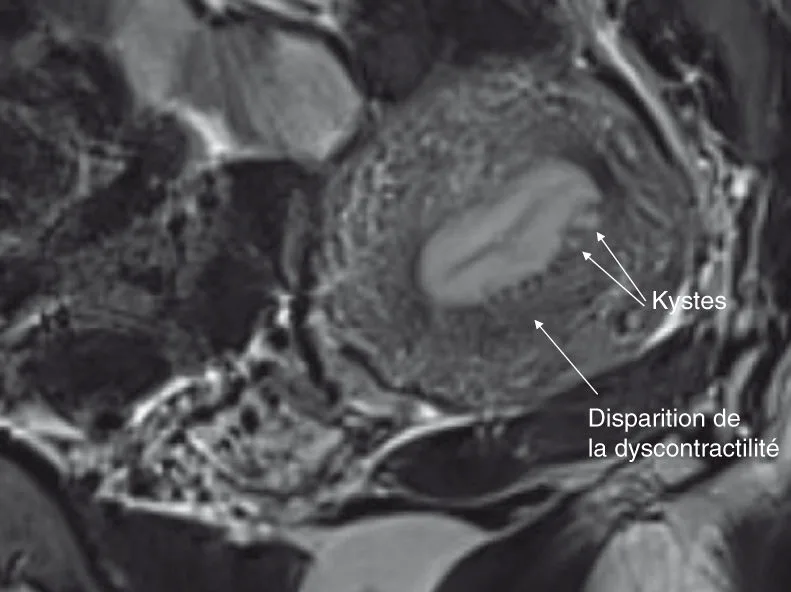

directs : irrégularités des berges de l'endomètre, microkystes en hypersignal T2, prédominant dans les zones de fragilité endomyométriale maximale, soit en postérieur sur la ligne médiane à hauteur du fond de l'endomètre et en regard des cornes endométriales (figures 6.1 et 6.2) ;

Figure 6.2. Dix-sept ans, dysménorrhée avec AS, ménorragies. Deuxième T2 sagittal, coupes de 2 mm. Source : Dr Petit.